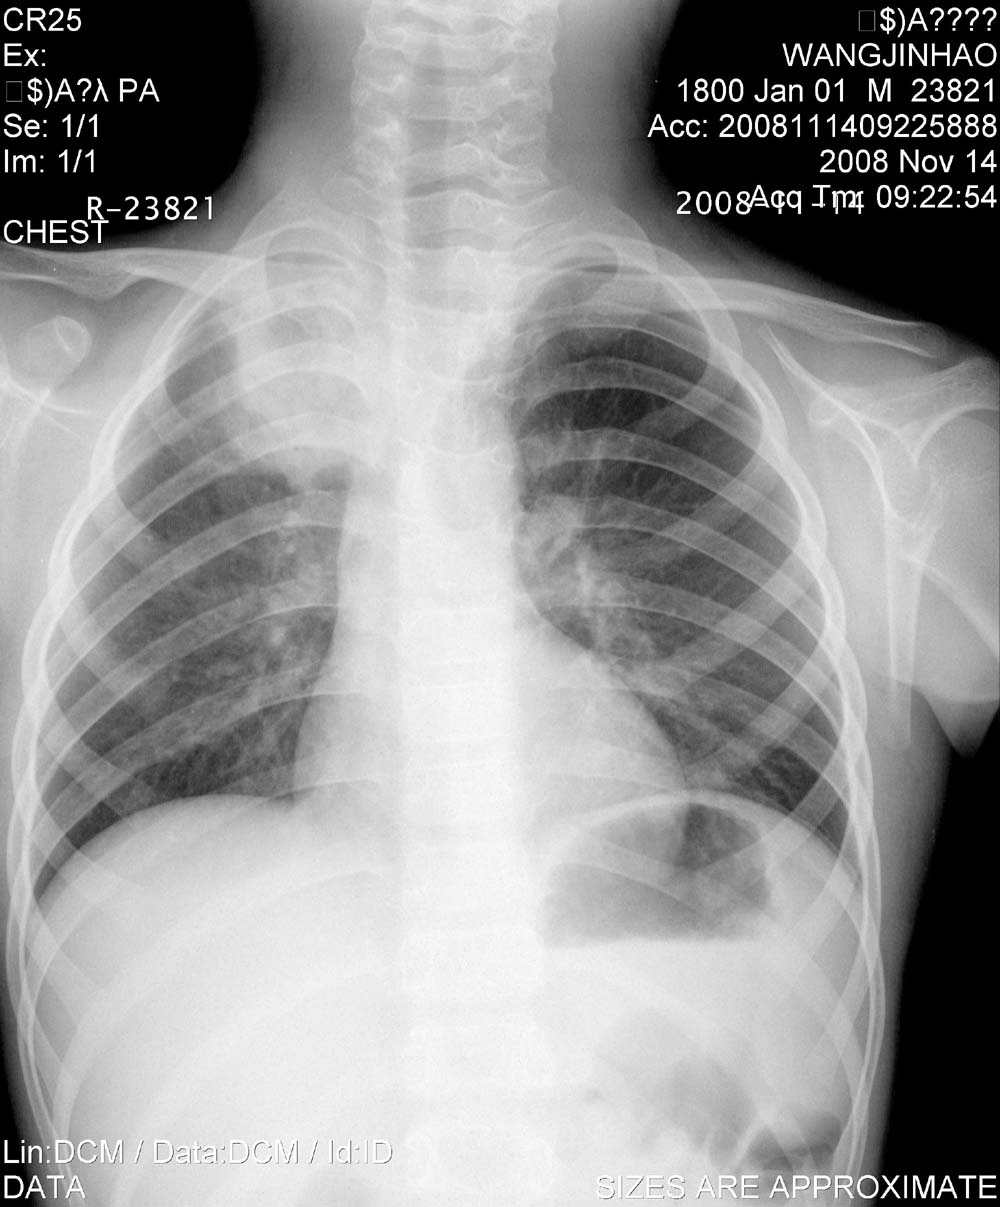

标题: PED1647:男,10岁,发热咳嗽5天就诊,请会诊。

男,10岁,发热咳嗽5天就诊,38-39度,血沉90    wbc12000,ttp(—)治疗6天无好转,复查胸片肺似有播散。

锁骨上下区,片状阴影,边界尚清,中等密度,治疗后胸片,右肺透光度下降,肺纹理增多增粗,象结核,参考。

原发性的肺结核之肺发灶有消散快且自消散的特点,本例前后两张片对比后片右肺门较前片有所增大,考虑淋巴结肿大可能.所以不除外原发三联征及肺门淋巴结核转变.